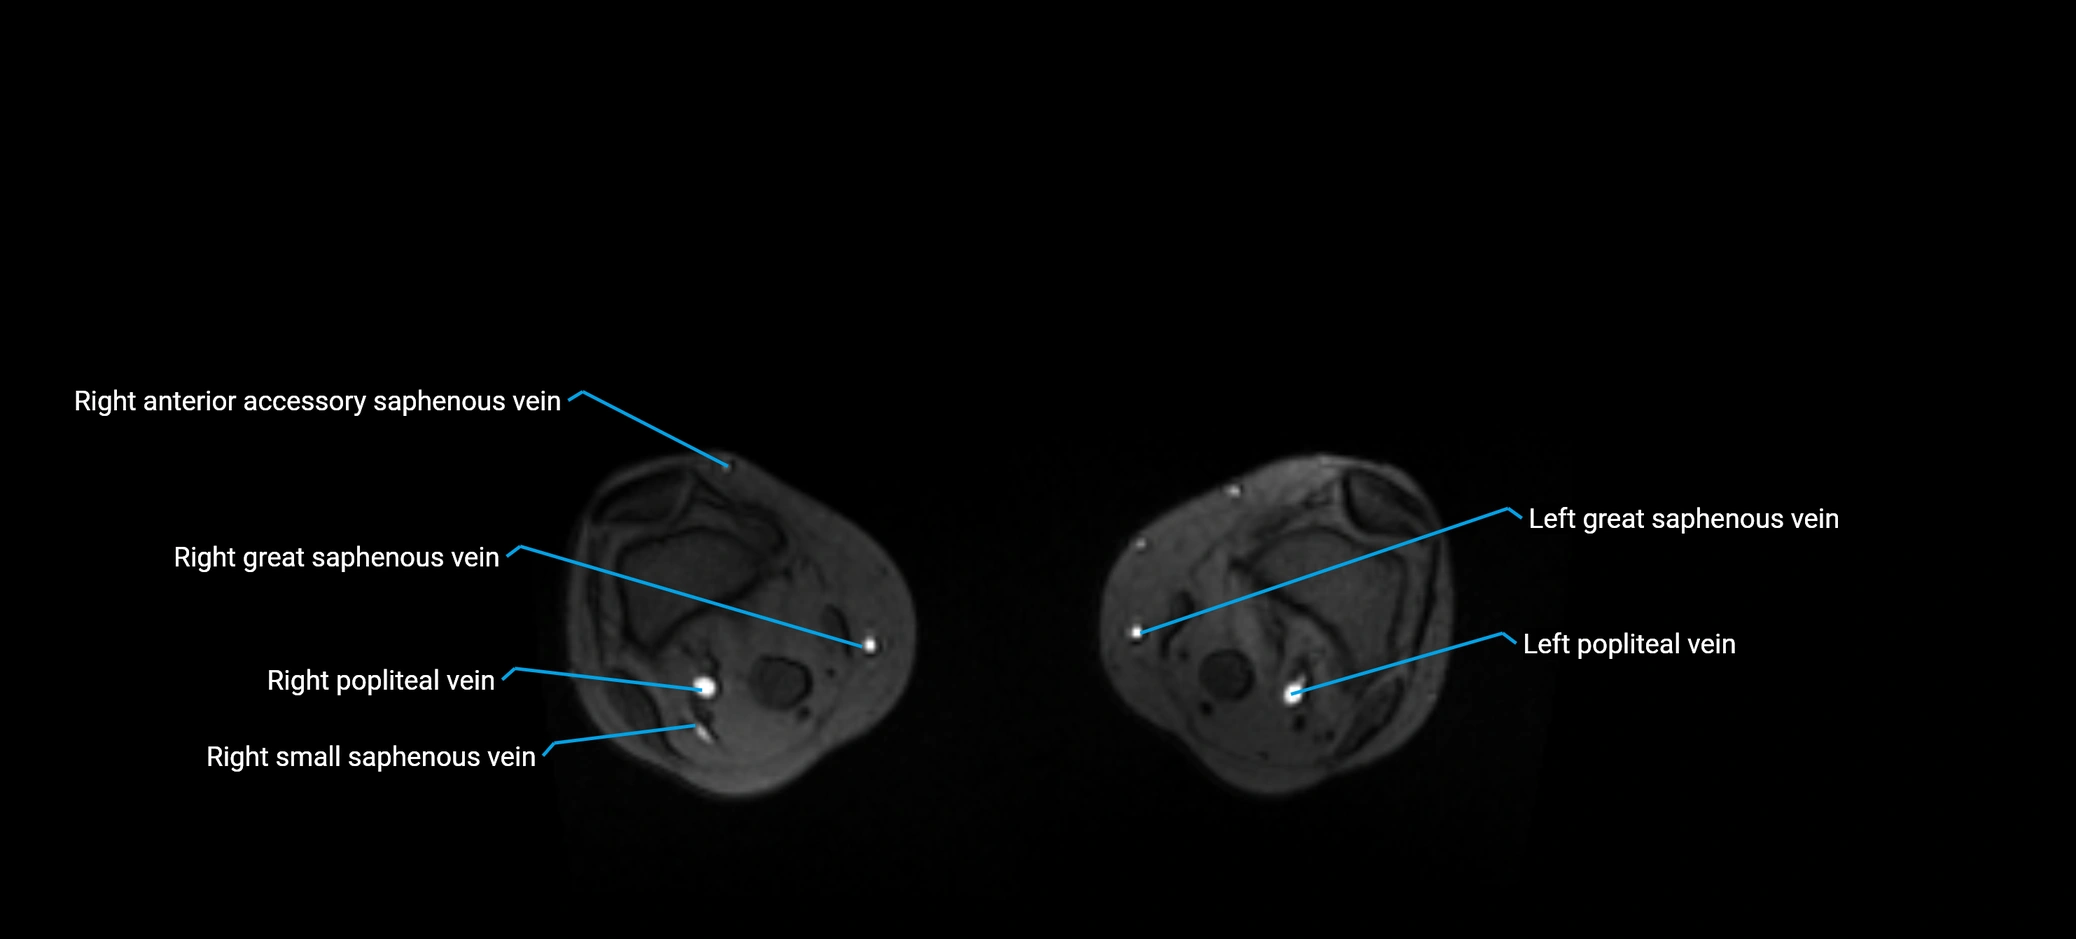

MRI image

image